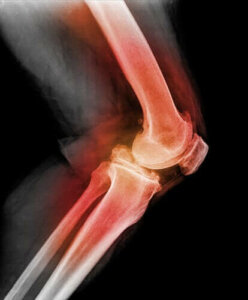

Polvilumpion sijoiltaanmenon diagnosoimiseksi lääkäri tunnustelee polvea ja taivuttaa polvea liikuttaen sitä eri suuntiin. Käyttämällä röntgenkuvausta, magneettikuvausta (MRI) tai tietokonetomografiaa (CT) lääkärit voivat nähdä kuvia siirretystä polvilumpiosta ja muista polvivammoista.